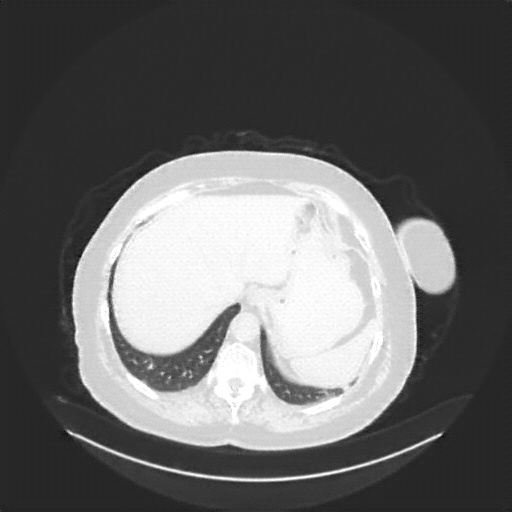

Reconstructed NATIVE CT scan (cycle consistency)

Full window (WL 1023.5, WW 4095 β†’ Low βˆ’1024, High +3071)

Lung window (WL -600, WW 1500 β†’ Low βˆ’1350, High +150)

Mediastinum window (WL 40, WW 400 β†’ Low βˆ’160, High +240)